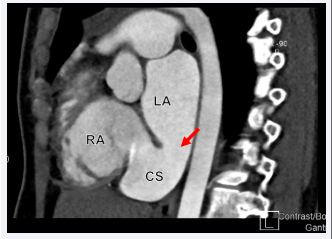

Patient was taken to the catheterization laboratory for ASD secundum type closure using Amplatzer device under TEE guidance. However, during procedure the multipurpose catheter crossed very inferiorly at the level of the coronary sinus (CS) into the LA. The left upper pulmonary vein identified very easily as well as a small CS vein, which is draining from the great cardiac vein. TEE showed that the multipurpose catheter in the LA, however, it did not go through the previously mentioned secundum ASD, raising the possibility of different co-existing septal defect. Procedure was aborted and patient was scheduled for CCTA to better define the septal defect and rule out the presence of PLSVC. CCTA showed a large ASD inferiorly, representing an UCS. The defect is large, measuring 24 mm in length, and both the superior and inferior vena cava are intact. The pulmonary veins drain in the LA. The right pulmonary veins emerge from a single trunk, while the left pulmonary veins emerge from a very short trunk that splits into two branches early on (Figures 6-9).

Cardiac computed tomography angiography (CCTA) in  sagittal display showing a communication between the RA and LA  representing unroofed CS (Arrow). CS, Coronary Sinus.

Figure 7: Cardiac computed tomography angiography (CCTA) in sagittal display showing a communication between the RA and LA representing unroofed CS (Arrow). CS, Coronary Sinus.

Cardiac computed tomography angiography (CCTA) in  sagittal displays showing dilated RA, ASD (Yellow Arrow), and  unroofed CS (Red arrow).

Figure 8: Cardiac computed tomography angiography (CCTA) in sagittal displays showing dilated RA, ASD (Yellow Arrow), and unroofed CS (Red arrow).